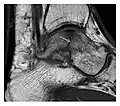

Fatigue fractures are more frequent in women which may be due to the relatively smaller bones of women. Moreover, pregnancy is a well-recognized risk factor for femoral neck fatigue fracture. While fibular and metatarsal fractures have a low risk of complications, other sites including the femoral neck, midanterior tibia, navicular, talar, and other intraarticular fractures are prone to complications such as delayed union, nonunion, and displacement. The site of the insufficiency fracture may be specific to the activity: for example, rugby and basketball players are more prone to navicular fractures, while gymnasts have a higher risk for talar fractures (Figure 7). Long distance runners are at increased risk for pelvic, tibial (Figures 8 and 9), and fibular fractures. In the military, calcaneus (Figure 10) and metatarsals are the most commonly cited injuries, especially in new recruits. Billiard players are at risk for upper limb fractures (Figure 11).[1]

Figure 8: Proximal diaphyseal fatigue fracture of the tibia in a 20-year-old man with a history of regular jogging. (a) Lateral radiograph shows no obvious fracture lines but a subtle localized medial tibial cortex periosteal reaction (arrows). (b) Sagittal reformatted CT image acquired 1-month after the radiograph shows a linear hypoattenuation in the tibial cortex (arrowhead), as well as obvious periosteal thickening (arrows). (c) Sagittal T2-weighted fat-saturated image acquired the same day shows an area of hyperintensity spreading over the proximal tibia (arrows), which is consistent with the presence of proximal tibial fracture.[1]